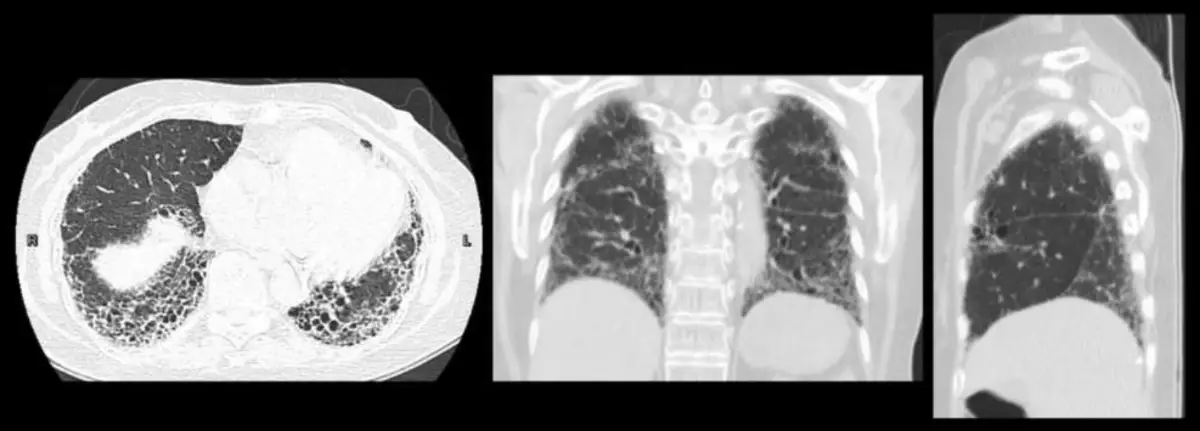

一位66歲女性,風濕免疫科確診為硬皮症(systemic sclerosis),因活動性喘至胸腔科門診就診。胸部電腦斷層掃描影像如附圖。經過風濕免疫科治療半年之後,病人咳嗽加劇,活動性喘更明顯,追蹤肺功能顯示用力肺活量(FVC)降低4%,一氧化碳肺瀰散量(DLCO)降低8%。胸部電腦斷層掃描,顯示新的蜂窩狀變化以及牽拉性支氣管擴張嚴重程度增加。關於此患者何者為錯誤?(1) 此患者肺功能已達漸進性肺纖維化(Progressive Pulmonary fibrosis, PPF)之標準(2) 影像表現為非特異性間質性肺炎(Non-Specific Interstitial Pneumonia)(3) 針對此患者目前已有充分臨床證據支持Pirfenidone之抗纖維化療效(4) 結締組織疾病相關的間質性肺病(CTD-ILD)產生漸進性肺纖維化之比例,最常見的是紅斑性狼瘡(SLE),其次是硬皮症 圖片描述

• 影像特徵:電腦斷層 (CT) 顯示雙側下肺葉、肋膜下出現明顯的網狀陰影 (reticulation) 及蜂窩狀變化 (honeycombing),並伴隨牽拉性支氣管擴張 (traction bronchiectasis)。

• 型態判讀:蜂窩狀變化 (Honeycombing) 是 UIP (Usual Interstitial Pneumonia) 型態的典型特徵。雖然 SSc-ILD 最常見的型態是 NSIP (主要為磨玻璃影 GGO,保留肋膜下,無蜂窩狀變化),但此病患影像明確顯示蜂窩狀變化,且題目文字提及「新的蜂窩狀變化」,故影像型態應為 UIP pattern,而非 NSIP。UIP pattern 在 SSc-ILD 中預後較差。

• (2) 影像表現為非特異性間質性肺炎(Non-Specific Interstitial Pneumonia)錯誤

• NSIP 的影像特徵為磨玻璃影 (GGO)、網狀陰影,通常伴隨肋膜下保留 (subpleural sparing),且定義上不應出現蜂窩狀變化 (honeycombing)

• 題目影像及文字均明確指出有「蜂窩狀變化」,這是 UIP pattern 的特徵。雖然 NSIP 是 SSc 最常見的表現,但此例為較嚴重的 UIP 表現。

2. SSc-ILD 影像:最常見為 NSIP (GGO, subpleural sparing),但約 25-30% 為 UIP (Honeycombing),UIP 預後較差。